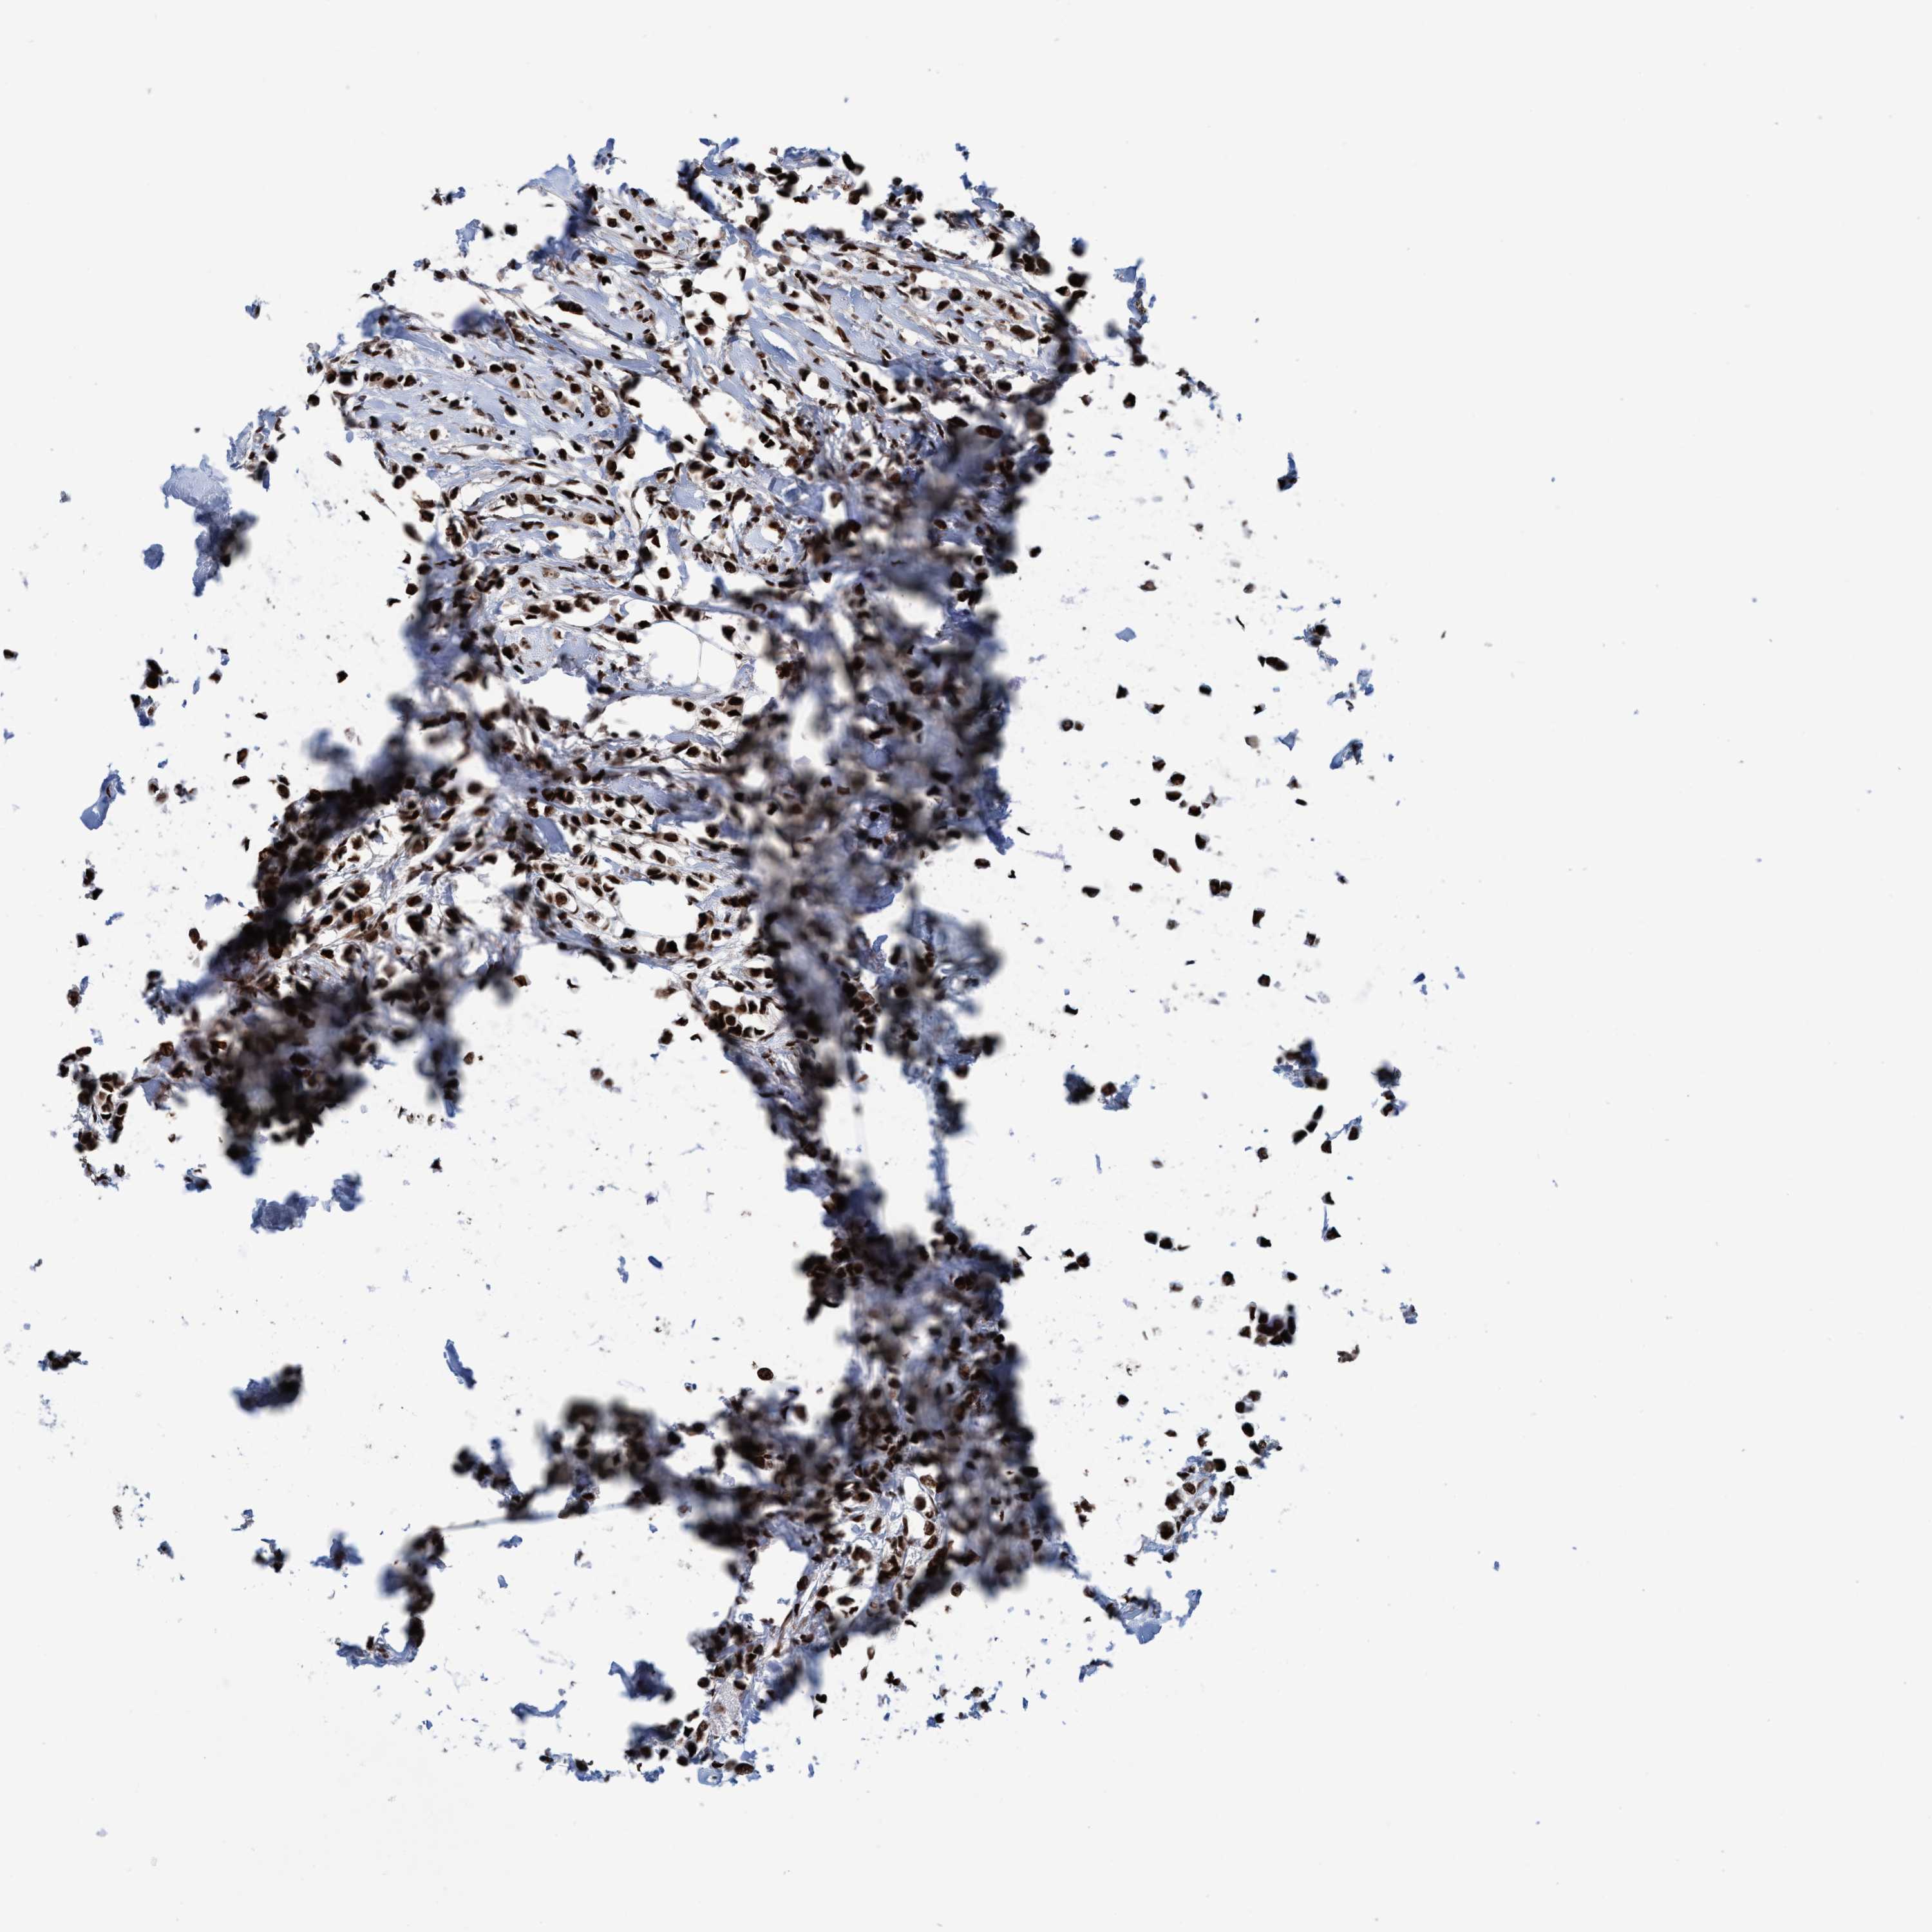

CANCER BREAST CANCER Show tissue menu

BRCA TCGA BRCA VALIDATION PROTEIN EXPRESSION